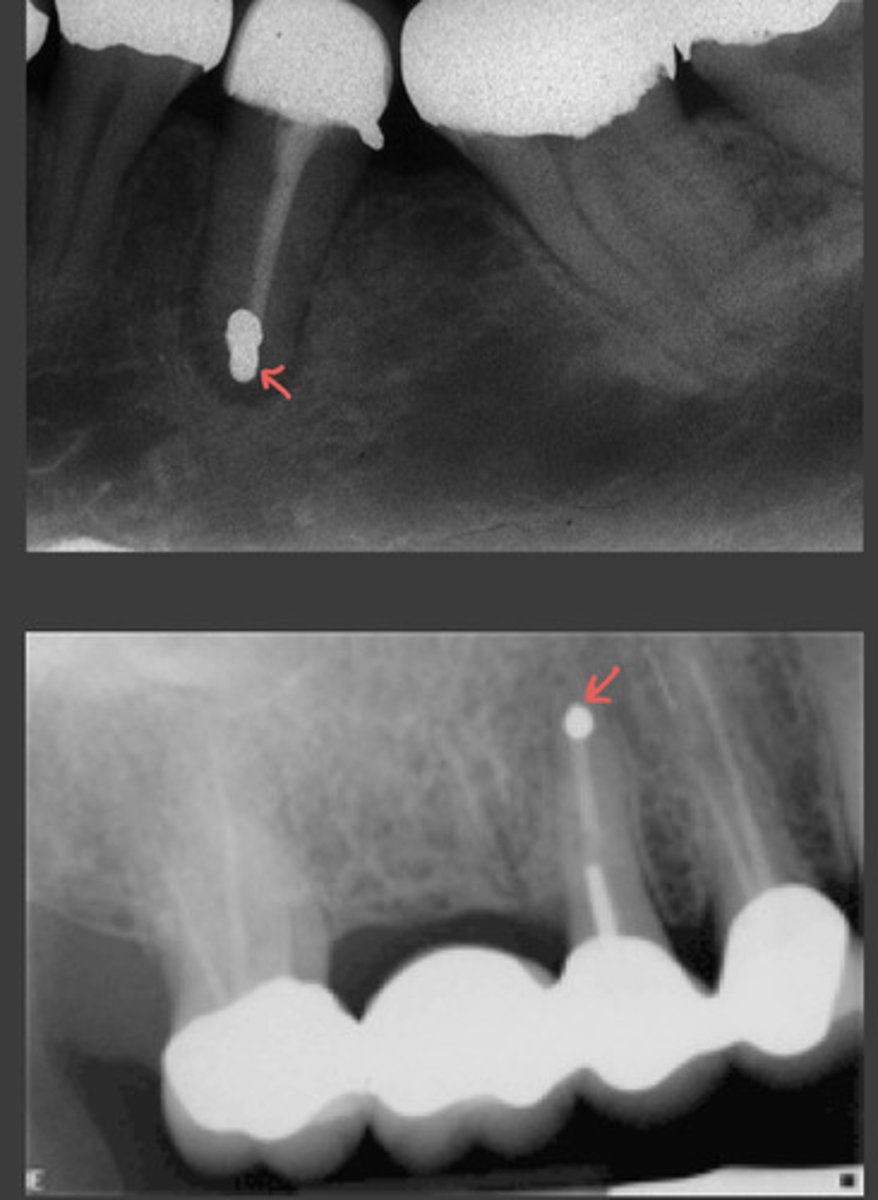

apicoectomy